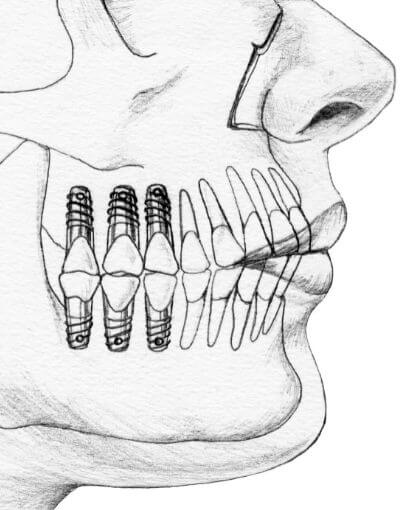

L'impianto dentale consiste nella sostituzione della radice naturale del dente mancante con una vite in titanio inserita nelle ossa mascellari. All'impianto è applicato un perno moncone che sostiene la corona avvitata o cementata; in questo modo viene ricreato il dente nella sua struttura interna ed esterna.

impianti arcata dentale

modello impianto dentale